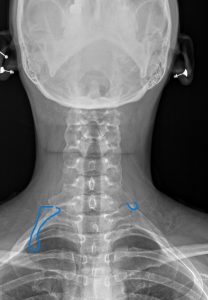

We are committed to enhancing patient care by delivering top-tier medical imaging evaluations and reports consistently. Our team of board-certified radiologists brings specialized expertise in diagnostic imaging, with a particular focus on chiropractic radiology that specializes in spine and musculoskeletal imaging. We strive to provide not just readings, but invaluable consultations, ensuring each patient receives the best that modern radiology has to offer. Our dedication to accuracy, speed, and reliability in off-site image interpretations sets us apart as trusted partners in healthcare.